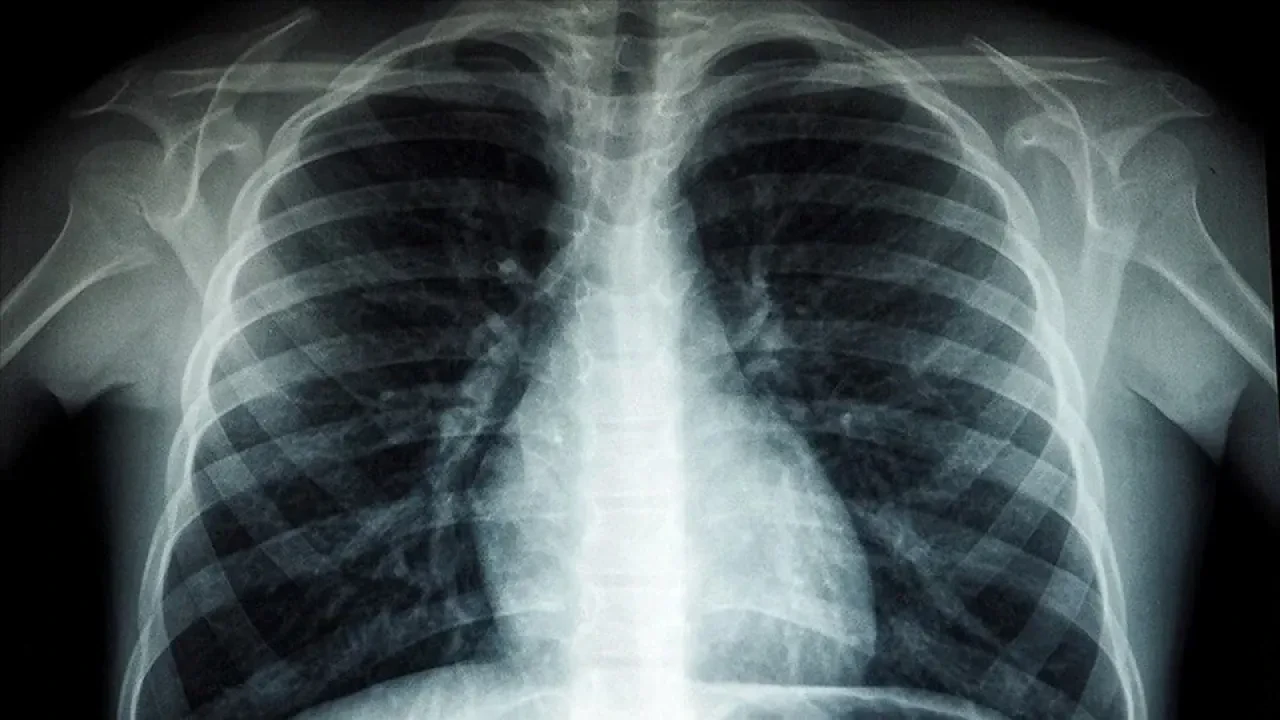

Tüberküloz, genellikle akciğerleri etkileyen bir bakterinin neden olduğu, hava yoluyla bulaşan bir hastalık ve başlıca risk faktörleri arasında yetersiz beslenme, HIV, alkol bağımlılığı, sigara kullanımı ve diyabet yer alır.